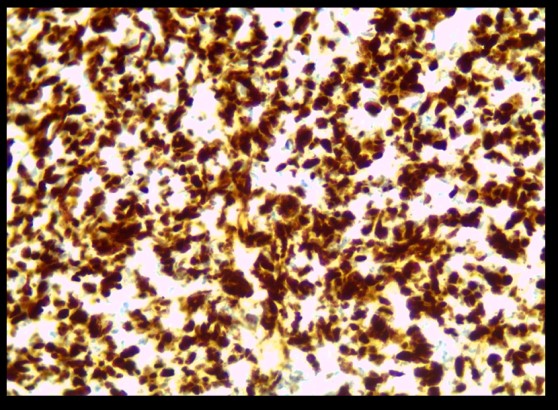

Figure1 : TNE bien différenciée G1

Figure 4 :TNE grade1 ki estimé à 2%.